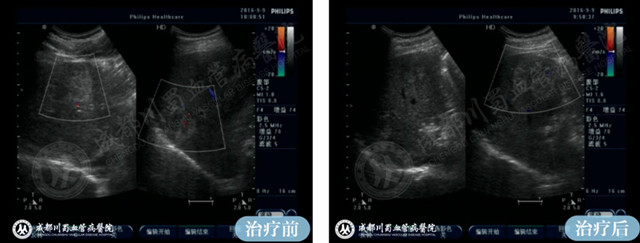

3.影像学检查

为了进一步确认诊断,医生可能会建议患者进行超声波检查、CT扫描或MRI等影像学检查。这些检查能够清晰地显示肝脏内部的结构和病变情况,为准确诊断提供有力支持。